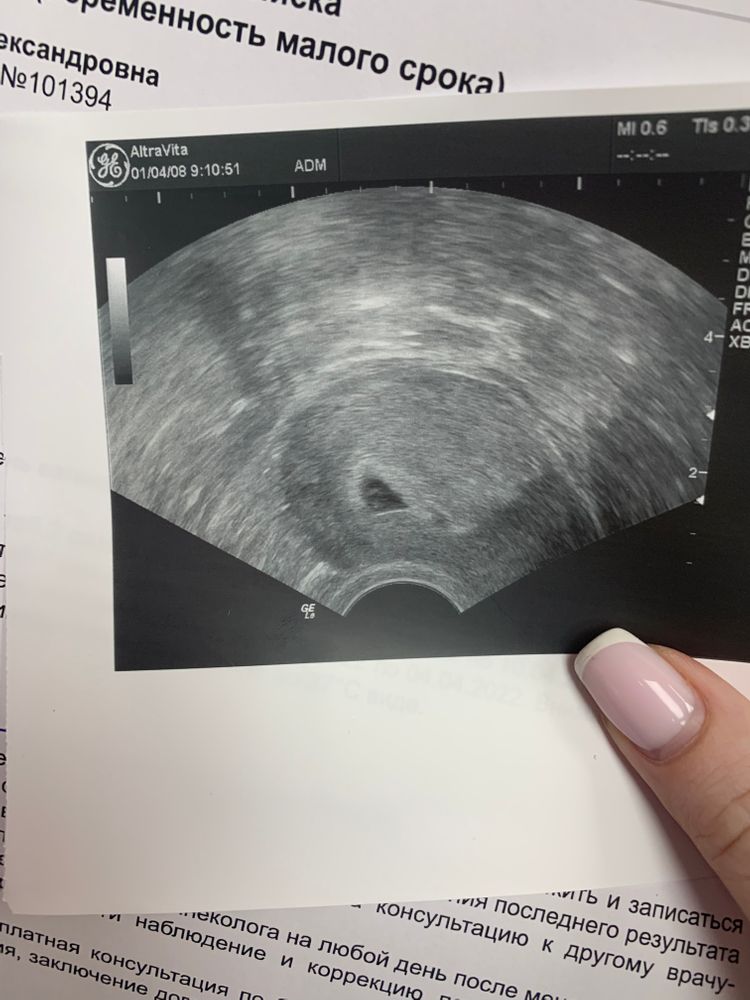

Вчера были на узи 🥰 ох девочки , как же я волновалась, я ехала и плакала всю дорогу туда , не знаю 🤷♀️ почему. В итоге все соответствует сроку (какому не сказала) ПЯ 9 мм и желточный мешочек ❤️ через недельку уже можно увидеть эмбриончик 😍😇 я очень счастлива, верю в своего малыша 🤰🤞🙏после вб, для меня услышать, что пя в матке это уже победа 🙌